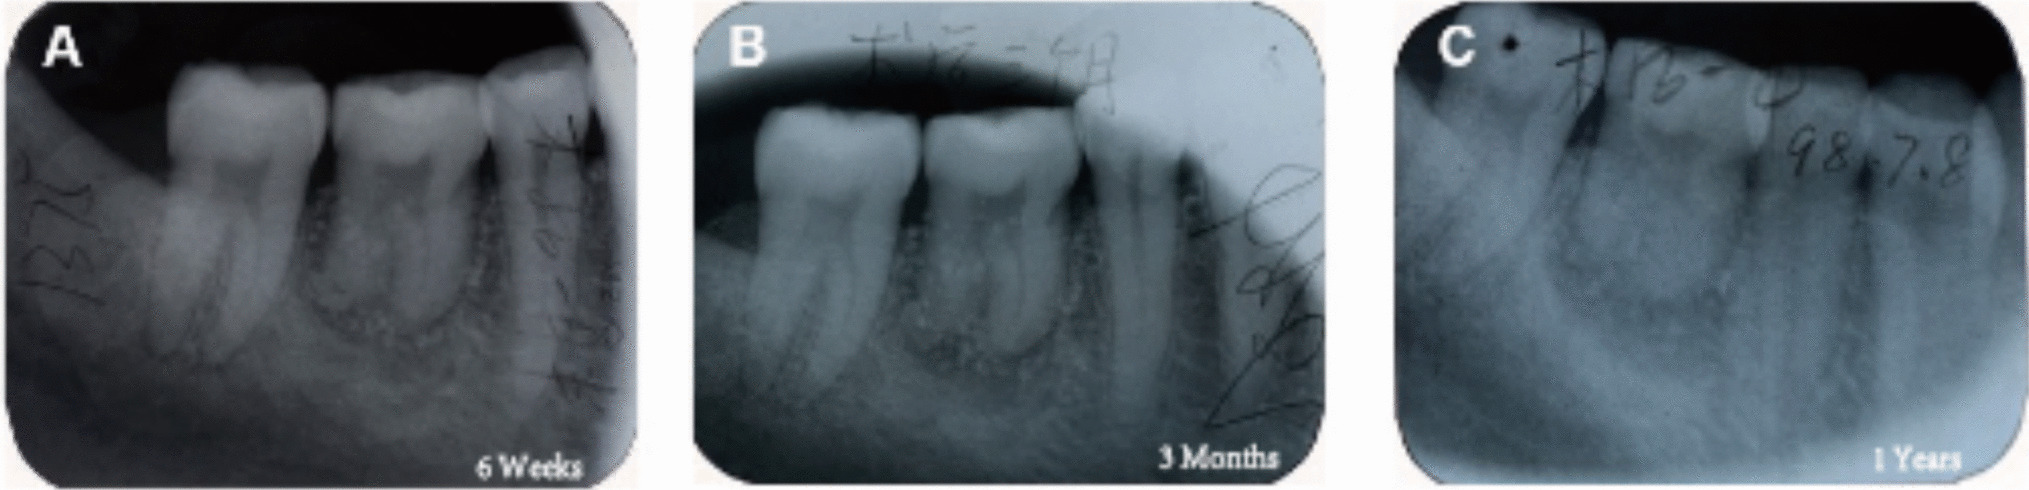

The surgical procedure was essentially the same as Case 1. The patient was followed up 6 months after transplantation, during which no significant pain or discomfort was reported. Imaging examinations revealed that the transplanted root had begun to form gradually, with the alveolar bone tightly integrated with the root (Fig. 15C). No apparent periapical lesions were observed. Consequently, the fixed ligature wire was removed, and monitoring continued, with RCT planned if necessary.

Fig. 15

A immediate postoperative (apices undeveloped) (B) two weeks postoperative (apices not yet completely closed) (C) six months postoperative (apices developed, distal caries involved.) (D) one year postoperative (apical foramen closed and caries filled.) (E) twenty years postoperative (residual root remained, alveolar socket reconstructed) e: twenty years postoperative (intraoral photograph)

One year later, follow-up evaluations indicated well-developed roots, a tendency for closure of the apical foramen was observed. Throughout this period, the patient experienced no discomfort and demonstrated good proprioceptive function. An intraoral examination and imaging revealed caries in the distal-medial region of the crown, which was restored with a filling (Fig. 15D). Unfortunately, during the patient’s visit 20 years post-grafting, it was noted that the grafted tooth had deteriorated to a stump due to untreated caries (Fig. 15E).